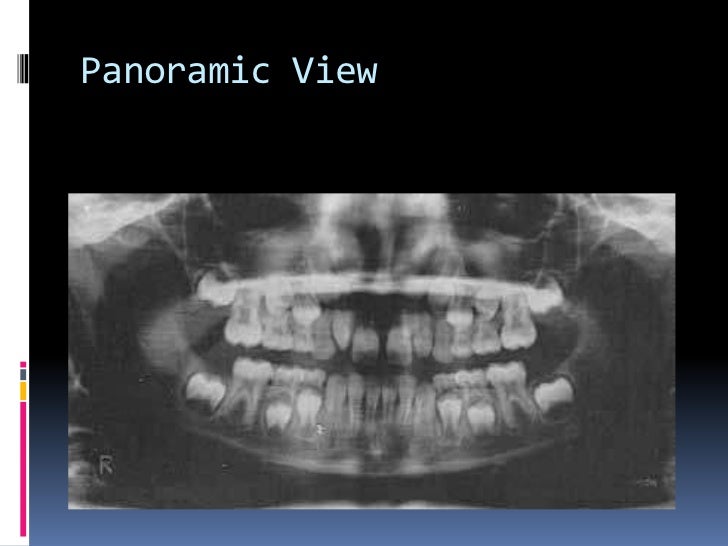

Panoramic Radiographs Dental Definition at Richard Maston blog Types Of Radiographs Dental Find out how they are used, what they show, and how they are safe. Below, we will explore the most common types of dental radiographs, both intraoral and extraoral, and their applications in dental practice. Intraoral (inside the mouth) or extraoral (outside the mouth), helping your dentist create a full picture of your. These tools enable dentists to. Types Of Radiographs Dental.

Types of dental radiographs in children Types Of Radiographs Dental Find out how they are used, what they show, and how they are safe. Below, we will explore the most common types of dental radiographs, both intraoral and extraoral, and their applications in dental practice. Intraoral (inside the mouth) or extraoral (outside the mouth), helping your dentist create a full picture of your. These tools enable dentists to. Types Of Radiographs Dental.

Types of dental radiographs in children Types Of Radiographs Dental These tools enable dentists to. Intraoral (inside the mouth) or extraoral (outside the mouth), helping your dentist create a full picture of your. Find out how they are used, what they show, and how they are safe. Below, we will explore the most common types of dental radiographs, both intraoral and extraoral, and their applications in dental practice. Types Of Radiographs Dental.